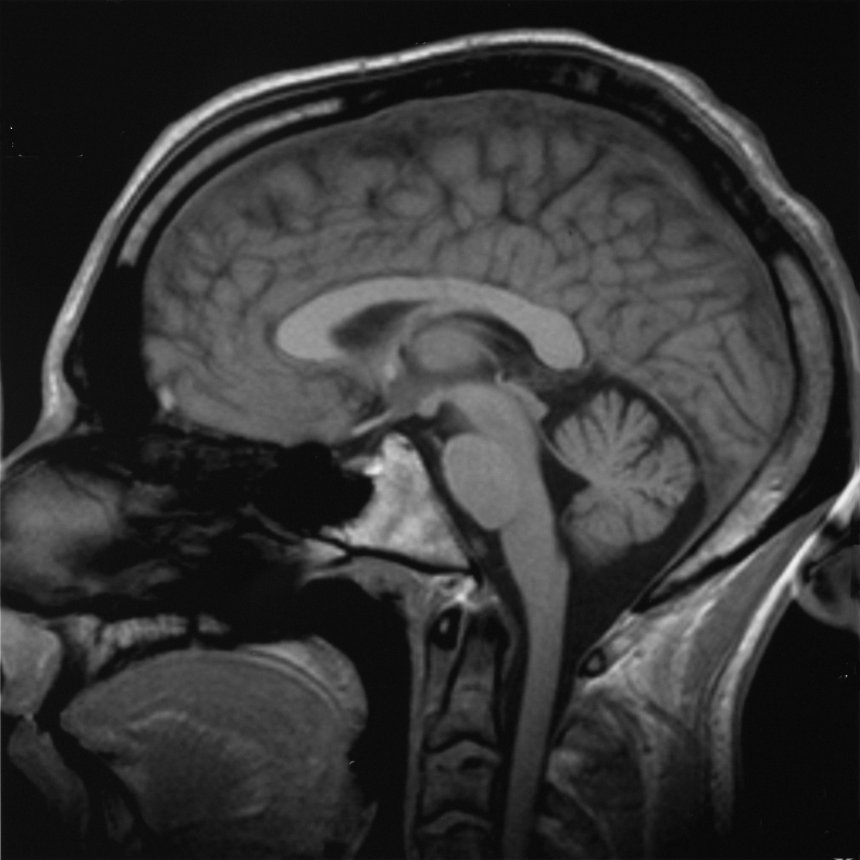

- 의료 영상: 자기 공명 영상(MRI), X-ray, CT 스캔 등 의료 진단에 필수적인 영상 기술을 다룬다.

의료/생물의학 영상은 의료 기기의 주요 부분이다. 이 분야는 임상의가 육안으로는 볼 수 없는 것들(크기 및/또는 위치 때문)을 직접 또는 간접적으로 "볼" 수 있도록 하는 것을 다룬다. 여기에는 초음파, 자성, 자외선, 방사선학 및 기타 수단을 활용하는 것이 포함될 수 있다.내비게이션 유도 장비는 뇌에 카테터를 삽입하거나 영양 튜브 삽입 시스템과 같은 전자기 추적 기술을 활용하기도 한다. 예를 들어, ENvizion Medical의 ENvue는 경장 영양 튜브 삽입을 위한 전자기 내비게이션 시스템이다. 이 시스템은 외부 필드 생성기와 여러 EM 수동 센서를 사용하여 디스플레이를 환자의 신체 윤곽에 맞춰 조정하고, 영양 튜브 팁의 위치와 방향을 실시간으로 볼 수 있도록 하여 의료진이 GI관에 정확하게 삽입하도록 돕는다.[15]

영상 기술은 종종 의학적 진단에 필수적이며, 일반적으로 병원에서 발견되는 가장 복잡한 장비이다. 여기에는 투시 촬영, 자기 공명 영상 (MRI), 핵의학, 양전자 방출 단층 촬영 (PET), PET-CT 스캔, X-ray 및 CT 스캔과 같은 투사 방사선 촬영, 단층 촬영, 초음파, 광학 현미경, 전자 현미경 등이 있다.